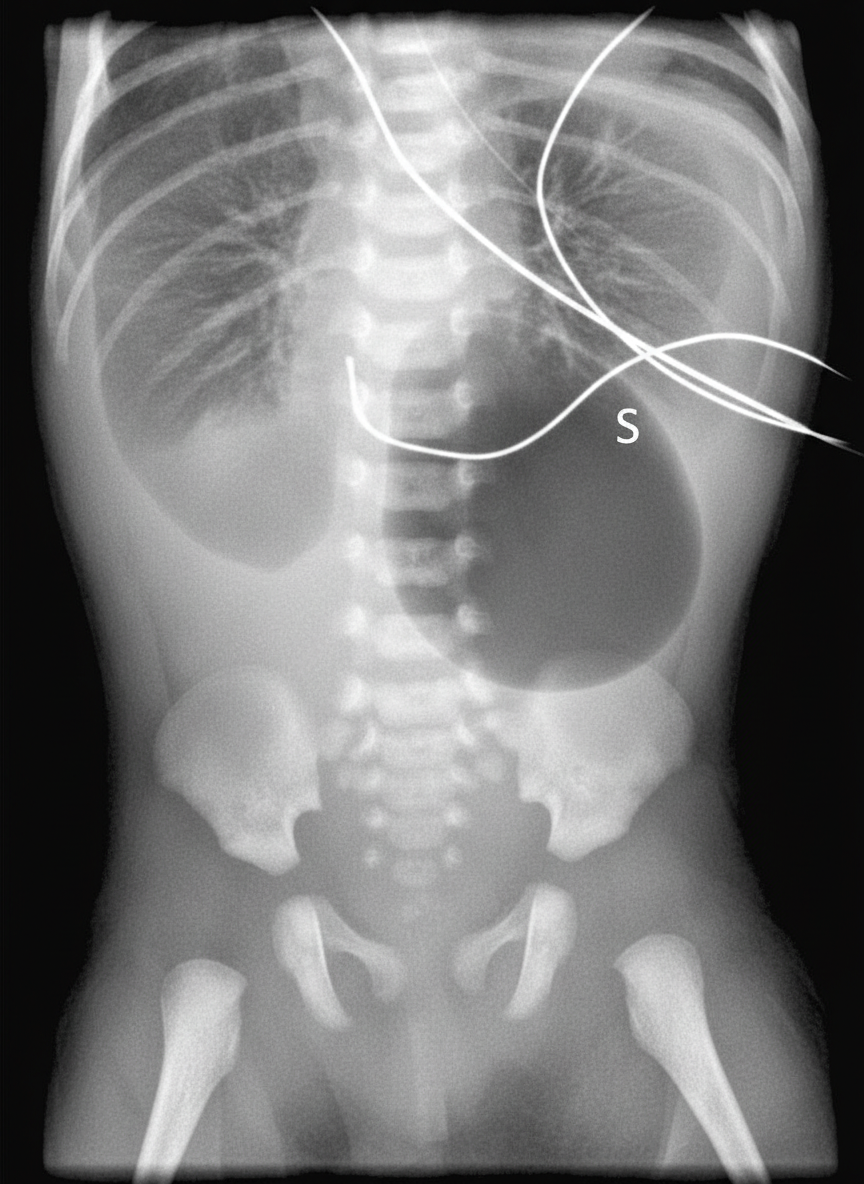

A 40-year-old woman brings her 2-day-old infant to the pediatrician’s office for a routine checkup. She tells the pediatrician that her baby vomits a greenish-yellow fluid after every feeding session. She has not been very successful in feeding him due to this problem. She also says that her baby has not passed stool since they left the hospital. On examination, the pediatrician observes that the baby has a flat facial profile and small eyes. The epicanthal folds are prominent and the palms have a single transverse crease. His abdomen is distended with high-pitched bowel sounds. The pediatrician orders an abdominal radiograph, the film is shown in the picture. Which of the following best explains the physical and clinical features exhibited by this infant?

Explanation: ***Trisomy*** - The combination of **facial dysmorphism** (flat facial profile, small eyes, prominent epicanthal folds), a **single transverse palmar crease**, and **gastrointestinal obstruction** (vomiting greenish-yellow fluid, abdominal distension, high-pitched bowel sounds, failure to pass stool) strongly points to **Down syndrome (Trisomy 21)**. - The abdominal radiograph shows a **double-bubble sign**, which is characteristic of **duodenal atresia**, a common congenital anomaly seen in infants with Trisomy 21. *Monosomy* - **Monosomy** refers to the absence of one chromosome from a pair. The most common human monosomy compatible with life is **Turner syndrome (Monosomy X)**, which affects females. - Turner syndrome presents with distinct features like **short stature**, **webbed neck**, and **gonadal dysgenesis**, which are not present in this infant. *Genomic imprinting* - **Genomic imprinting** is an epigenetic phenomenon where certain genes are expressed in a **parent-of-origin-specific manner**. Examples include **Prader-Willi** and **Angelman syndromes**. - These syndromes have specific clinical features (e.g., **hyperphagia** and developmental delay in Prader-Willi, severe intellectual disability and **ataxia** in Angelman) that do not match the infant's presentation. *Anticipation* - **Anticipation** is a phenomenon in genetics where the symptoms of a genetic disorder become **more severe** and appear at an **earlier age** in successive generations. - This typically occurs in disorders caused by the expansion of **trinucleotide repeats**, such as **Huntington's disease** or **myotonic dystrophy**, and does not explain these congenital anomalies. *Locus heterogeneity* - **Locus heterogeneity** describes a condition or trait caused by mutations in **different genes** at **different chromosomal loci**. - While many complex genetic disorders exhibit locus heterogeneity, it primarily explains **inheritance patterns** and does not directly describe the specific clinical and radiographic findings of a single patient with multiple congenital anomalies.